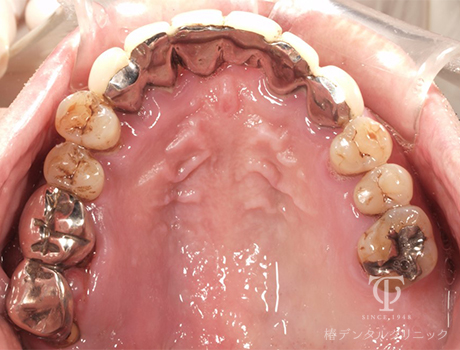

術後の上顎内冠

-

術前レントゲン

インプラント治療後レントゲン

- 症状

- 右上の痛み

- 治療期間

- 約1年半

- 治療費用

- (上顎)インプラント治療:473,000円×2

(上顎)AGCテレスコープ義歯:1,500,000円

(下顎)インプラント治療:473,000円×2

右上の歯が痛いということで来院されました。インプラントとAGCテレスコープという方法でかみ合わせを再構築しました。